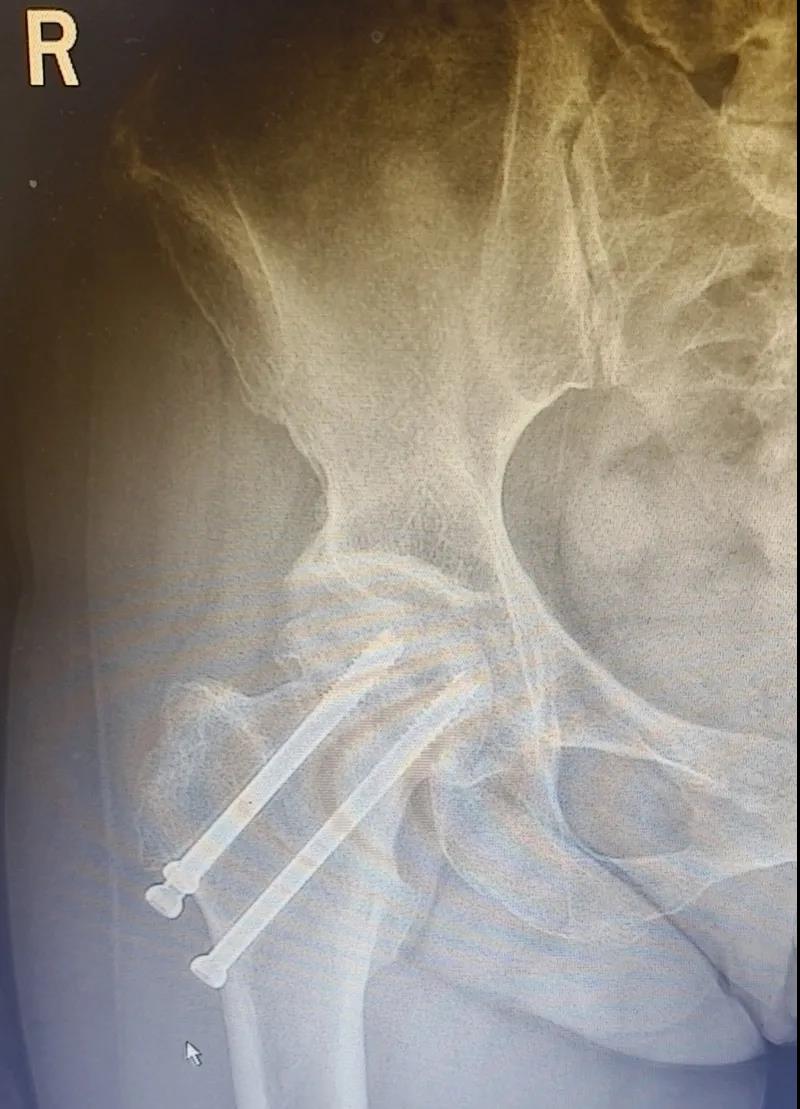

據(jù)李女士自述,自己于3年前因外傷致右股骨頸骨折,當時在其他醫(yī)院做了右股骨頸骨折閉合復位螺釘內(nèi)固定術(shù),一年后右髖出現(xiàn)疼痛并逐漸加重,且休息不能緩解,行走時就像有座山壓身上一樣。

結(jié)合病癥表現(xiàn)及影像顯示,李女士被診斷為“右股骨頸骨折術(shù)后股骨頭壞死”,需要盡快做手術(shù)。

(△術(shù)前影像,右股骨頸骨折內(nèi)固定術(shù)后股骨頭壞死)